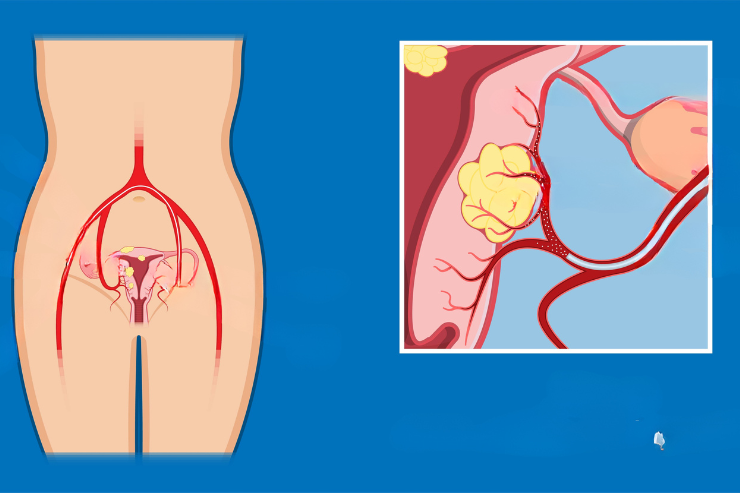

Uterine Artery Embolization

Uterine Artery Embolization is a minimally invasive procedure used to treat uterine fibroids. It involves injecting tiny particles into the uterine arteries to block blood flow to the fibroids, causing them to shrink. This procedure helps alleviate symptoms such as heavy bleeding, pain, and pressure, providing a less invasive alternative to surgery.